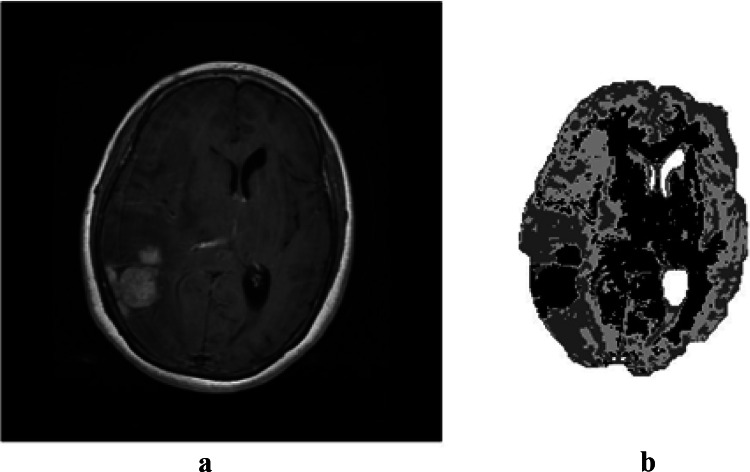

In this section, the aim is to segment MRI images of the brain, using the algorithms presented in the previous sections and comparing their performance. The proposed algorithms are applied on 50 images with two different types of tumors (30 MRI brain images contain the Meningioma tumor and 20 MRI brain images contain the pituitary tumor). These two types are different in shape and location. Figure 3 presents the result of the initial segmentation of the MRI brain image containing the Meningioma tumor using GA.

Fig. 3.

a Original image; b initial segmentation using GA